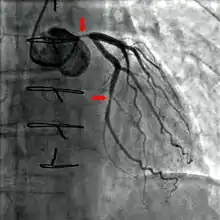

Coronary catheterization is one of the several cardiology diagnostic tests and procedures. Specifically, through the injection of a liquid radiocontrast agent and illumination with X-rays,[1] angiocardiography allows the recognition of occlusion, stenosis, restenosis, thrombosis or aneurysmal enlargement of the coronary artery lumens; heart chamber size; heart muscle contraction performance; and some aspects of heart valve function. Important internal heart and lung blood pressures, not measurable from outside the body, can be accurately measured during the test. The relevant problems that the test deals with most commonly occur as a result of advanced atherosclerosis – atheroma activity within the wall of the coronary arteries. Less frequently, valvular, heart muscle, or arrhythmia issues are the primary focus of the test.

If atheroma, or clots, are protruding into the lumen, producing narrowing, the narrowing may be seen instead as increased haziness within the X-ray shadow images of the blood/dye column within that portion of the artery; this is as compared to adjacent, presumed healthier, less stenotic areas.

For guidance regarding catheter positions during the examination, the physician mostly relies on detailed knowledge of internal anatomy, guide wire and catheter behavior and intermittently, briefly uses fluoroscopy and a low X-ray dose to visualize when needed. This is done without saving recordings of these brief looks. When the physician is ready to record diagnostic views, which are saved and can be more carefully scrutinized later, he activates the equipment to apply a significantly higher X-ray dose, termed cine, in order to create better quality motion picture images, having sharper radiodensity contrast, typically at 30 frames per second. The physician controls both the contrast injection, fluoroscopy and cine application timing so as to minimize the total amount of radiocontrast injected and times the X-ray to the injection so as to minimize the total amount of X-ray used. Doses of radiocontrast agents and X-ray exposure times are routinely recorded in an effort to maximize safety.